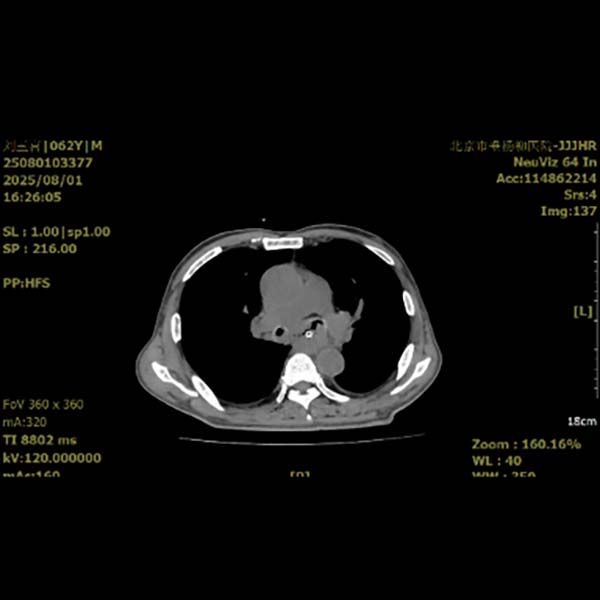

近日,清华大学附属垂杨柳医院胸外科接诊一位确诊为食管气管瘘的中年男性患者。其20日前出现吞咽困难,1周前突发不明原因发热伴频繁咳嗽、咳痰,体温最高达38.5℃。外院行胸部增强CT检查,提示食管占位合并食管气管瘘。

图1 术前影像